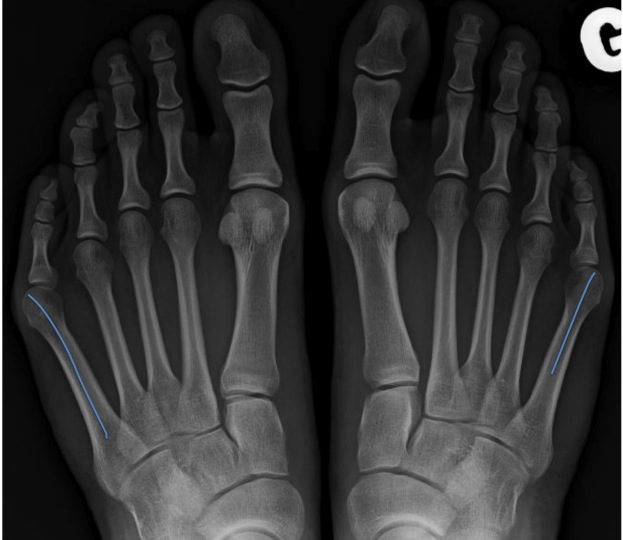

Si le traitement conservateur, basé sur des chaussures adaptées et des soins podologiques, ne suffit plus, on peut proposer une opération. C’est par une ostéotomie (ouverte ou percutanée) qu’on corrigera la déformation, dépendante du type de bunionette et analysée par une radiographie du pied en charge.

Type 1 : dans 33% des cas : augmentation de la taille de la tête du cinquième métatarsien situé sur le bord externe du pied : une réduction de volume sera recommandée.

Type 2 : dans 23% des cas : courbure latérale excessive du cinquième métatarsien ; une ostéotomie distale peut réajuster cette déformation.

Type 3 : dans 44% des cas : augmentation excessive de l’angle intermétatarsien 4-5 : une ostéotomie proximale ou une ostéotomie au niveau de la malformation permet de normaliser cet angle.